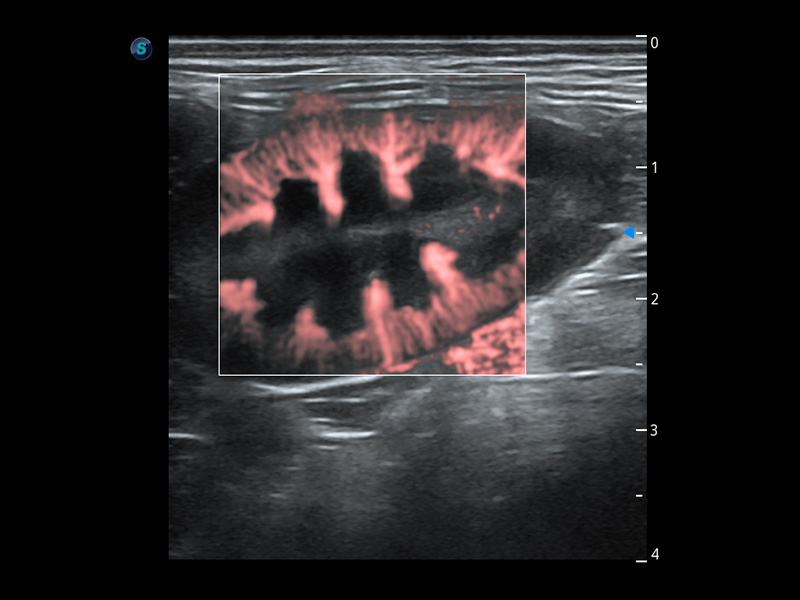

ProPet 60 作为一款高端台式动物超声设备,为动物医生的日常诊断提供了一系列贴合动物临床需求、解决临床实际问题的高级成像功能。凭借全系列高清探头,满足医生对腹部、心脏、生殖、浅表、肌骨等成像的所有需求,切实帮助您提升检查效率,提高诊断信心。

动物是人类最亲密的朋友和最值得信赖的伙伴。亚星官网也一直致力于探索动物专用的超声影像解决方案。 全新推出的ProPet系列,是亚星官网在动物超声影像智能化、专业化、精准化的一次跨越式革新。动物不能用言语来表述自己的不适,通过超声影像,ProPet系列搭建了动物医生与不同物种沟通的“桥梁”,为动物医生注入了“治愈之力”。